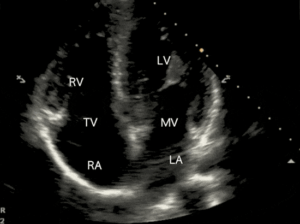

At Concierge Cardiology of MT, we firmly believe patients of all ages should have access to various options for heart screening. That’s why we offer heart screening services, including consultations, electrocardiograms (ECGs/EKGs), and echocardiograms (heart ultrasound). Dr. Hua, our experienced cardiologist, is passionate about providing the best care possible to our patients.